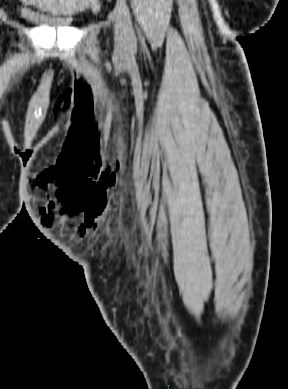

Figure 2 for case Necrotizing fasciitis ( RID3447 )

Figure 2